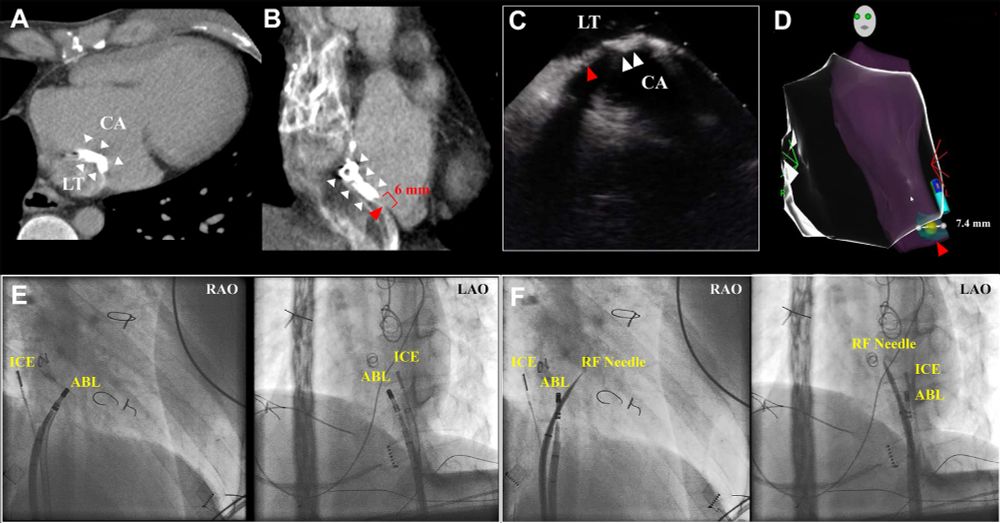

❤️ A novel puncture method combining intracardiac echocardiography and a 3D mapping system for catheter ablation after a lateral tunnel Fontan operation ⬇️

cjcpc.ca/article/S277...

#CJCPC #OpenAccess